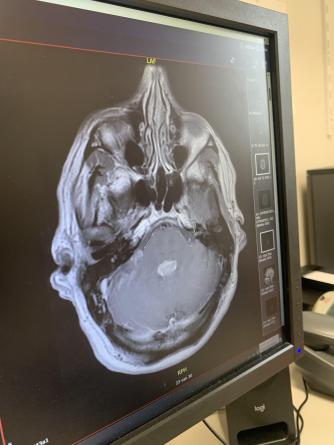

Ik heb gisteren te horen gekregen dat er op de scan van mijn laatste drie-maandelijkse MRI, tumorgroei te zien is. Al weet ik dat vanwege de gradatie 4 de tumor terugkomt, was de schok enorm groot. Ik vond namelijk dat ik goed bezig was, met ondermeer volgen KETO dieet, diverse supplementen (zelfs paddestoelen, energetische coach, integrale arts etc. Ik wil niet zeggen ‘voor niets’ maar zo voelt het wel. Zo dadelijk spreken wij mijn neuroloog, zien we de scan en bespreken de mogelijkheden. Ik ben benieuwd. Tot zover!

Update: er zitten kankercellen in mijn hersenvocht die zich overal kunnen nestelen. Dat is al gebeurd rechts in mijn achterhoofd, maar dat is niet het grootste probleem. Het ‘afvoerputje’ van het hersenvocht is verstopt geraakt met de k. cellen en dat is funest. Ik krijg nog wel een chemokuur als poging één en ander te stabiliseren maar dat is een hele kleine kans. Mocht het werken dan heb ik nog enkele maanden, anders enkele weken. Echt bizar dit! Niet te bevatten..